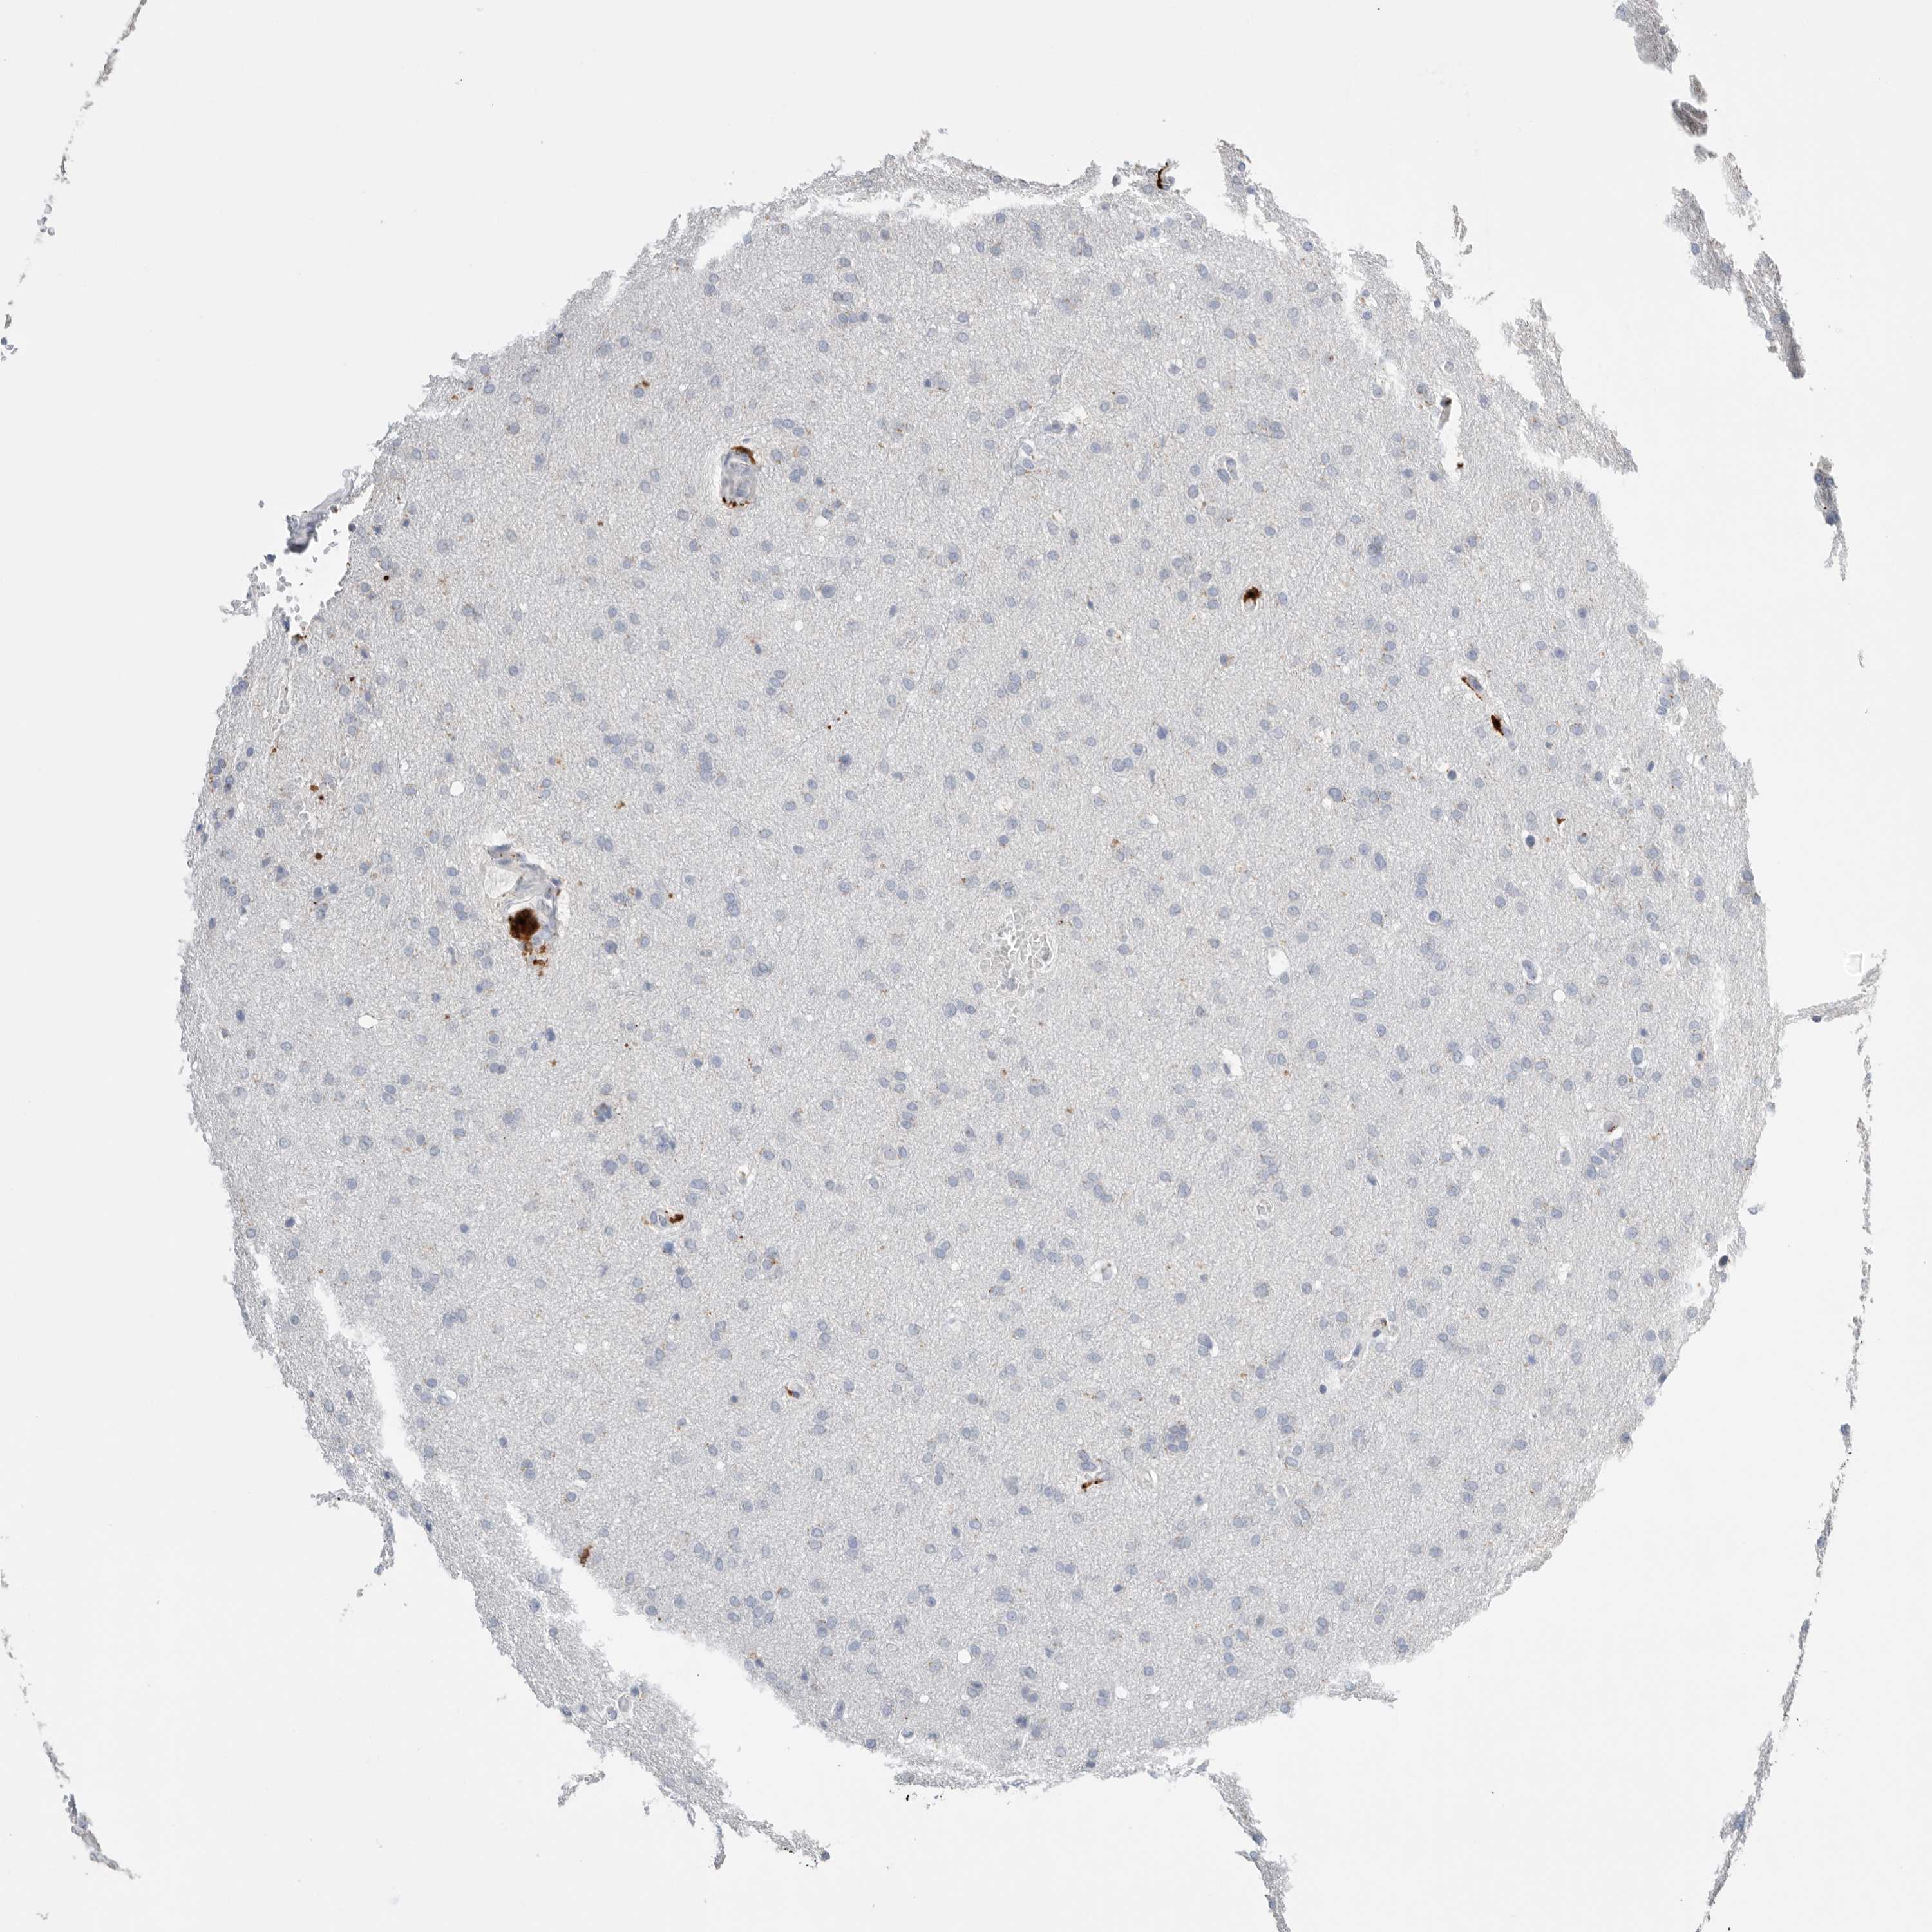

GLIOMA - Protein expressioni

A mouse-over function shows sample information and annotation data. Click on an image to view it in a full screen mode. Samples can be filtered based on level of antibody staining by selecting one or several of the following categories: high, medium, low and not detected. The assay and annotation is described here.

Note that samples used for immunohistochemistry by the Human Protein Atlas do not correspond to samples in the TCGA dataset.

Antibody stainingi

Antibody staining in the annotated cell types in the current human tissue is reported as not detected, low, medium, or high, based on conventional immunohistochemistry profiling in selected tissues. This score is based on the combination of the staining intensity and fraction of stained cells.

Each image is clickable and will lead to virtual microscopy that enables deeper exploration of all samples and also displays staining intensity scores, fraction scores and subcellular localization as well as patient and tissue information for each sample.

Antibody HPA025226

Antibody CAB019296

Staining

High

Medium

Low

Not detected

Intensity

Strong

Moderate

Weak

Negative

Quantity

>75%

75%-25%

<25%

None

Location

Nuclear

Cytoplasmic/membranous

Cytoplasmic/membranous,nuclear

Glioma, malignant, High grade

Glioma, malignant, Low grade